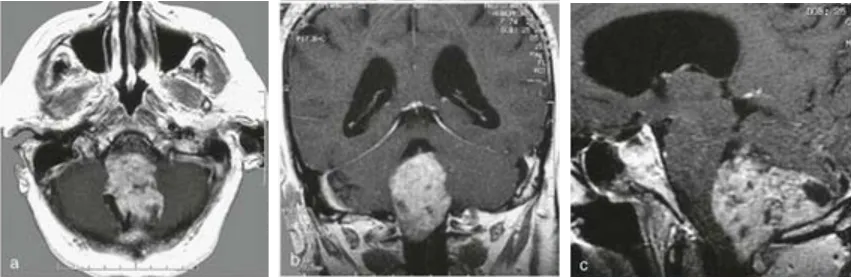

病例一:74岁女性患者

因持续性剧烈头痛与进行性步态不稳就诊,日常行走需搀扶。术前MRI(a-c)显示巨大肿瘤完全占据第四脑室,向下延伸至颅颈交界区,压迫脑干,手术风险高。肿瘤病理为良性室管膜瘤,经INC巴教授手术实现全切(术后MRI见e、f),未新增神经功能障碍。